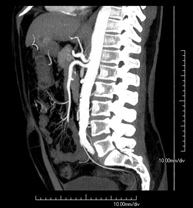

- Angio-TC aorta abdominal

Prueba diagnóstica no invasiva que consiste en el estudio de la arteria aorta abdominal obteniendo imágenes de alta definición anatómica mediante el empleo de un equipo de TC (Tomografía Computarizada) y de contraste yodado. La calidad de las imágenes permite realizar reconstrucciones en 2D y 3D gracias a estaciones de trabajo especializadas en el estudio arterial. Está indicado en aquellos pacientes con enfermedad vascular (aterosclerosis), en aneurismas de aorta, en pacientes con dolor abdominal de posible origen vascular, en estudios pre-quirúrgicos de lesiones adyacentes a la aorta abdominal como "mapa" vascular, etc. La información obtenida de forma no invasiva es indispensable para los pacientes que requieren tratamiento percutáneo o quirúrgico. En aquellos pacientes que solo requieren un seguimiento de las lesiones vasculares, esta técnica es la técnica no invasiva de elección junto con la angio-RM.

Prueba diagnóstica no invasiva que consiste en el estudio de la arteria aorta abdominal obteniendo imágenes de alta definición anatómica mediante el empleo de un equipo de TC (Tomografía Computarizada) y de contraste yodado. La calidad de las imágenes permite realizar reconstrucciones en 2D y 3D gracias a estaciones de trabajo especializadas en el estudio arterial. Está indicado en aquellos pacientes con enfermedad vascular (aterosclerosis), en aneurismas de aorta, en pacientes con dolor abdominal de posible origen vascular, en estudios pre-quirúrgicos de lesiones adyacentes a la aorta abdominal como el "mapa" vascular, etc. La información obtenida de forma no invasiva es indispensable para los pacientes que requieren tratamiento percutáneo o quirúrgico. En aquellos pacientes que solo requieren seguimiento de las lesiones vasculares, esta técnica es la técnica no invasiva de elección junto con la angio-RM.